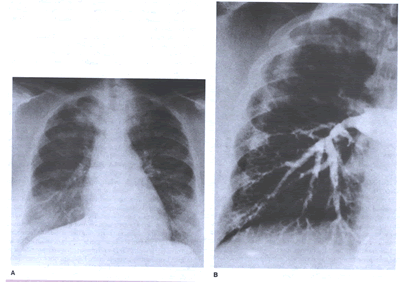

filling defect in a pulmonary artery establishes diagnosis(DIAGPEANGIOG-fig.9).

DIAGPEANGIOG-fig.9:: Pulmonary hypertension due to organized

clot in central pulmonary arteries. Dramatic relief after pulmonary

thromboendarterectomy. A. Chest radiograph. The right upper

lobe is strikingly hypoperfused, and the vasculature on the

left is quite prominent, reflecting redirection of the pulmonary

blood flow to open vessels. B. Angiogram. The flow to the right

upper lung is interrupted by the large central clot.